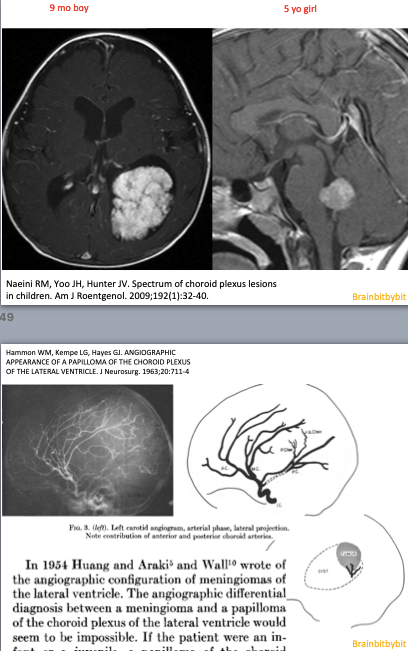

As a medical student the first thing about the brain I knew by heart was the ventricular system. It was so easy to remember: *Cerebrospinal fluid (CSF) gets produced by the choroid plexus in the lateral ventricles -> flows via the foramen of Monro to the 3rd ventricle -> from the 3rd ventricle via the aqueduct to the 4rd ventricle and then via L-Lateral foramina of Luschka and a M-Median foramen of Magendie to the subarachnoid space. *Granulations of Pacchioni in the subarachnoid space resorb CSF.

Figure 1 Coronal (above) and sagittal (below) T1 weighted images showing the lateral ventricles (lat), third (III) and fourth ventricle (IV) and several subarachnoid cisterns. The temporal horn of the lateral ventricle is anatomically close to the subarachnoid space, more specific the choroid fissure.